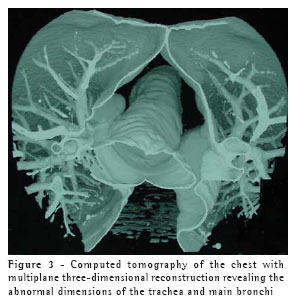

This treatment continued for four weeks, by which time the symptoms had been completely resolved. At that point, the patient was submitted to a computed tomography scan of the chest, which revealed that the areas of consolidation, although smaller in size, persisted in both lower lobes, and confirmed the abnormal widening of the trachea and main bronchi (Figures 1, 2 and 3). In the lower lobes, there was bilateral cylindrical bronchiectasis, which is consistent with a diagnosis of congenital tracheobronchomegaly, or Mounier-Kuhn syndrome. Pulmonary function tests revealed an increase in total lung capacity (123% of predicted) and residual volume (160% of predicted), with no other alterations. Currently, the patient remains asymptomatic, and has daily respiratory therapy sessions. Annual immunization against influenza has been recommended.

Congenital tracheobronchomegaly, or Mounier-Kuhn syndrome, is a rare clinical entity, described for the first time in 1932,(1) and characterized by marked tracheobronchial dilation and lower respiratory tract infections. It is predominantly found in male individuals in their 40s or 50s. Although the etiology of Mounier-Kuhn syndrome remains unknown, it is believed that it is related to a lack of smooth muscle and elastic connective tissue in the trachea and main bronchi, leading to herniation and even to the formation of diverticula between the cartilaginous rings. A finding of bronchiectasis, such as in the case in question, is uncommon.(2-3)

Diagnosis can usually be made by measuring the tracheal diameter, using only data from chest X-rays, in which the trachea can seen in profile and thus the diameter determined. Computed tomography of the chest, however, makes this measurement more precise. The limits are 3 cm for the transverse diameter of the trachea, and 2.4 cm and 2.3 cm for the transverse diameters of the main right and left bronchi, respectively.